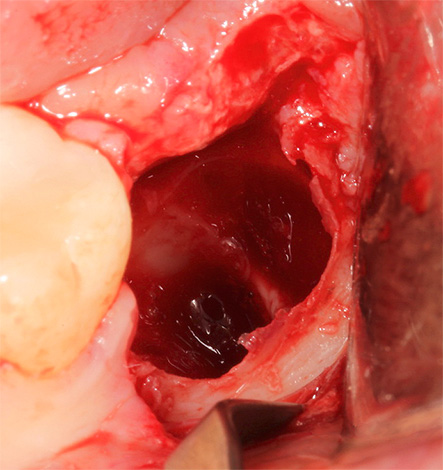

Depois de cortar as gengivas, separar as raízes com uma broca e extraí-las do buraco, o buraco é limpo de “sujeira”: resíduos de ossos, pedaços de dentes cariados, resíduos de raízes, serragem. Para fazer isso, as bordas afiadas do buraco são suavizadas com pinças de osso ou uma broca, a ferida é lavada com soluções anti-sépticas, um medicamento é colocado no buraco (de acordo com as indicações) e as bordas da ferida são suturadas. Recomendações são dadas ou é marcado um acompanhamento para monitorar a qualidade da cura.